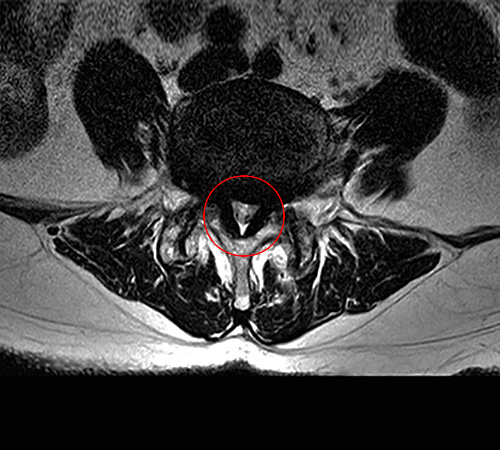

MRI 영상으로 봤을 때는 척추의 퇴행성 변화로 인해 황색인대가 부풀어오르기 시작하는 것을 협착증 초기로 봅니다. 그 다음 척추관 중앙의 공간이 30% 이상 막힌 것을 중기라고 판단하며, 척추관의 공간이 50% 이상 막혀서 심한 보행장애를 동반하는 것을 협착증 말기로 봅니다.